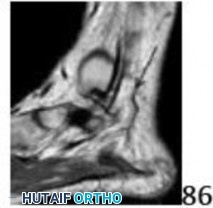

Learn more about ORTHOPEDIC MCQS 011 ANATOMY IMAGING and how to manage it. A stress or insufficiency fracture of the anterior calcaneus is the likely cause of persistent plantar and lateral foot pain, unresponsive to conservative treatment. MRI typically shows increased signal (edema) and abnormal trabecular patterns in the inferior anterior calcaneus. The accurate diagnosis question is a b in managing this condition effectively, particularly in overweight patients.

Q 1 1a 1b 1c 1d 1e A 43-year-old female factory worker has had a 6-month history of right plantar and lateral foot pain. She has pain with weight bearing and has difficulty standing at work. Management consisting of physical therapy, time off of work, and fracture boot immobilization has failed to provide relief. She is overweight and, as a result of the pain, cannot exercise to lose weight; thus she is getting worse instead of better. Examination reveals that the foot is not grossly swollen but is diffusely tender over the lateral, plantar, and medial hindfoot. The alignment is normal and the posterior calf muscles are mildly tight. A lateral radiograph is shown in Figure 1a and MRI scans are shown in Figures 1b through 1e. These findings are most consistent with which of the following?

DISCUSSION: The studies are most consistent with a stress fracture or insufficiency fracture of the anterior portion of the calcaneus. The radiograph shows normal findings. There is increased signal involving the inferior anterior aspect of the calcaneus on the T2-weighted images (Figures 1c through 1e), which is consistent with edema. There is also an abnormal trabecular pattern within this region with changes on the T1 and T2 images consistent with a stress or insufficiency fracture of the calcaneus. Whereas there is some increased signal from the os trigonum and the origin of the plantar fascia, these diagnoses are inconsistent with her symptoms. The MRI findings of osteomyelitis (decreased T1 signal and increased T2 signal) with secondary soft-tissue findings of adjacent soft-tissue ulcers, cellulitis, phlegmon, abscess, sinus tracts, or cortical bone destruction are not present. Complex regional pain syndrome has a wide spectrum of findings on MRI and is usually much more diffuse.

The Preferred Response to Question # 1 is 3.